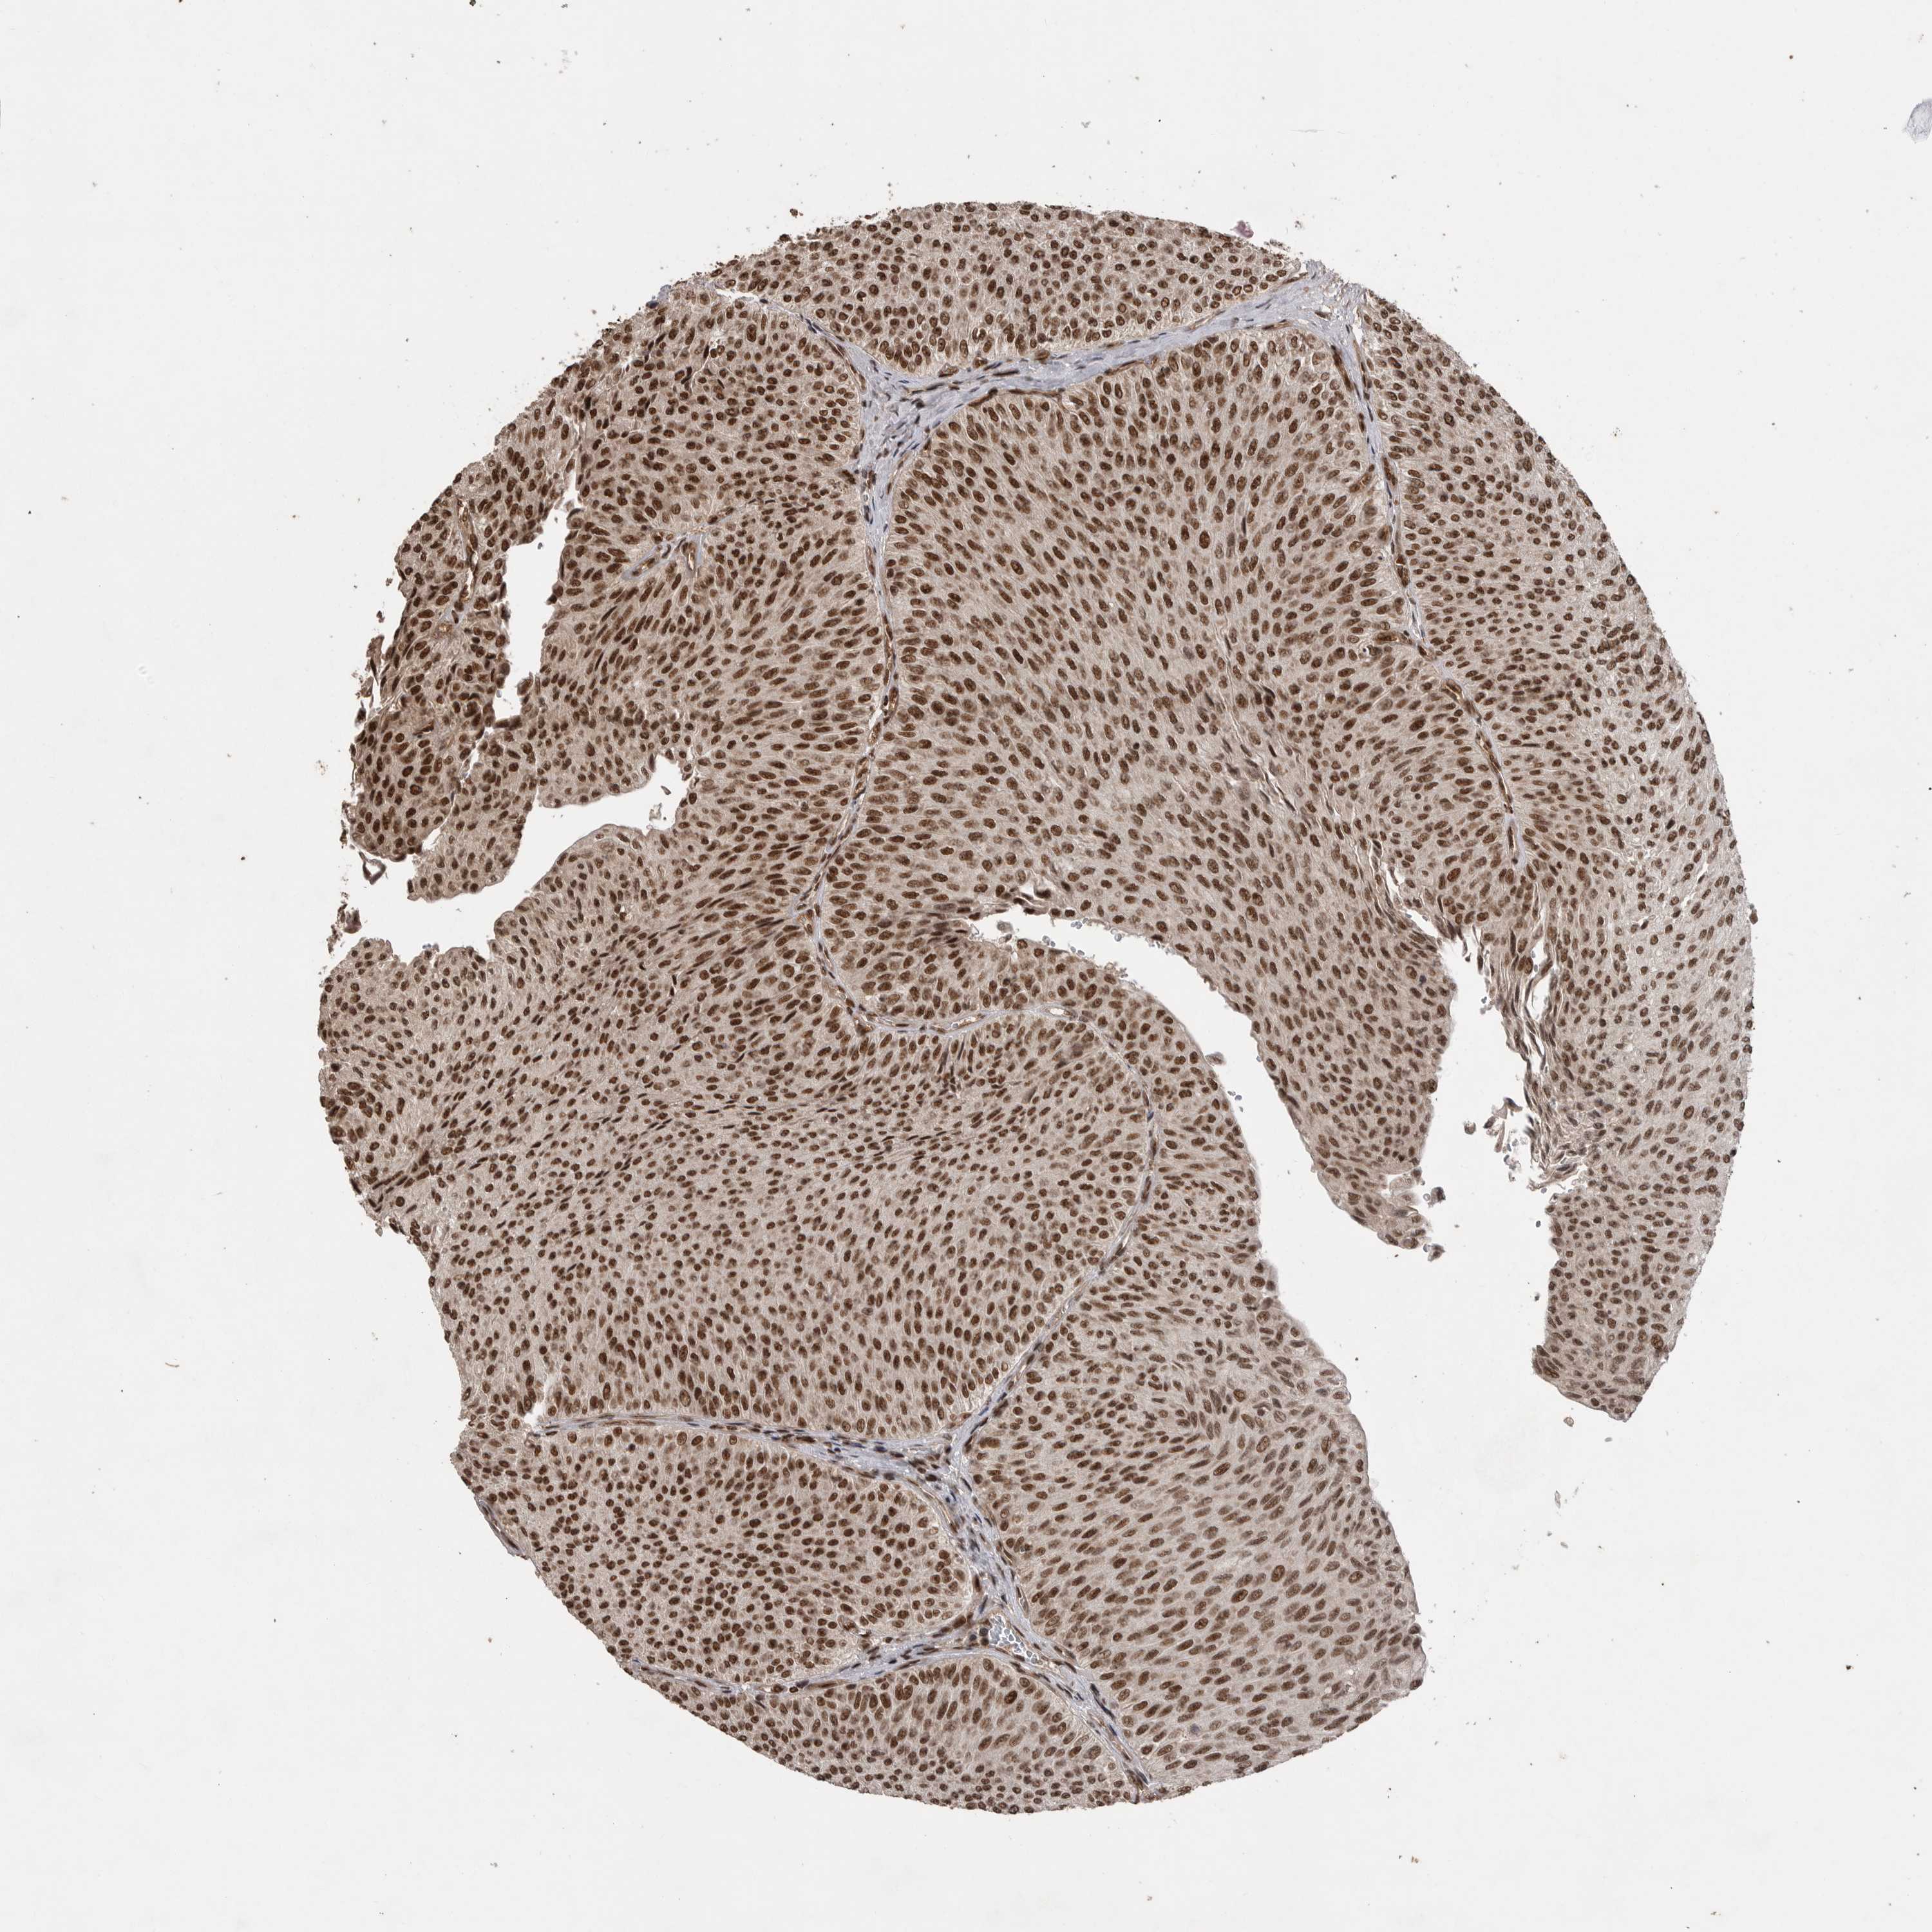

UROTHELIAL CANCER - Protein expressioni

A mouse-over function shows sample information and annotation data. Click on an image to view it in a full screen mode. Samples can be filtered based on level of antibody staining by selecting one or several of the following categories: high, medium, low and not detected. The assay and annotation is described here.

Note that samples used for immunohistochemistry by the Human Protein Atlas do not correspond to samples in the TCGA dataset.

Antibody stainingi

Antibody staining in the annotated cell types in the current human tissue is reported as not detected, low, medium, or high, based on conventional immunohistochemistry profiling in selected tissues. This score is based on the combination of the staining intensity and fraction of stained cells.

Each image is clickable and will lead to virtual microscopy that enables deeper exploration of all samples and also displays staining intensity scores, fraction scores and subcellular localization as well as patient and tissue information for each sample.

Antibody HPA027406

Antibody HPA027417

Antibody HPA027452

Staining

High

Medium

Low

Not detected

Intensity

Strong

Moderate

Weak

Negative

Quantity

>75%

75%-25%

<25%

None

Location

Nuclear

Cytoplasmic/membranous

Cytoplasmic/membranous,nuclear

Urothelial carcinoma, Low grade

Urothelial carcinoma, High grade